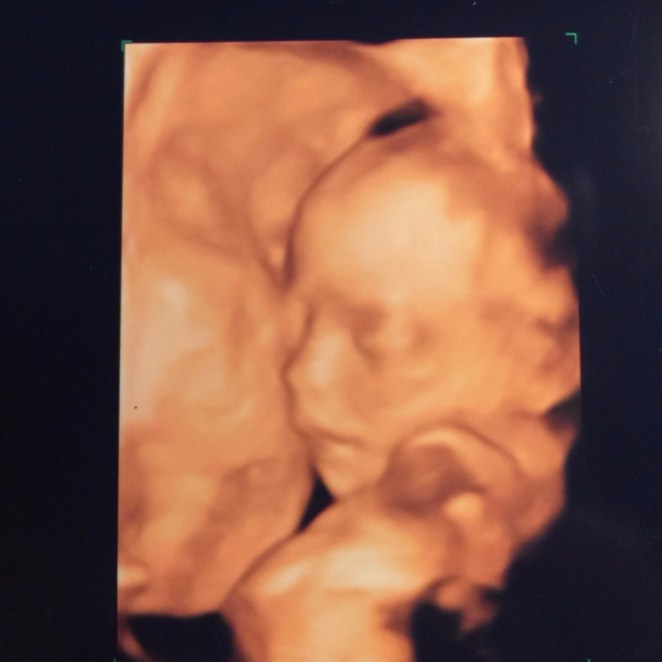

On a trip home for my birthday, we decided to check out one of the 3D/4D ultrasounds and are so glad we did!

She was moving and kicking and practicing breathing and it was amazing to see our little one so clearly. The tech was great about explaining everything and we walked away with clear confirmation that all is proceeding well and that she is, indeed, a girl. We also learned that she is 11 inches long! Afterwards, we checked out the baby shop and picked up a few fun baby items. Best birthday presents ever!

img_4205

Cuddle bug!